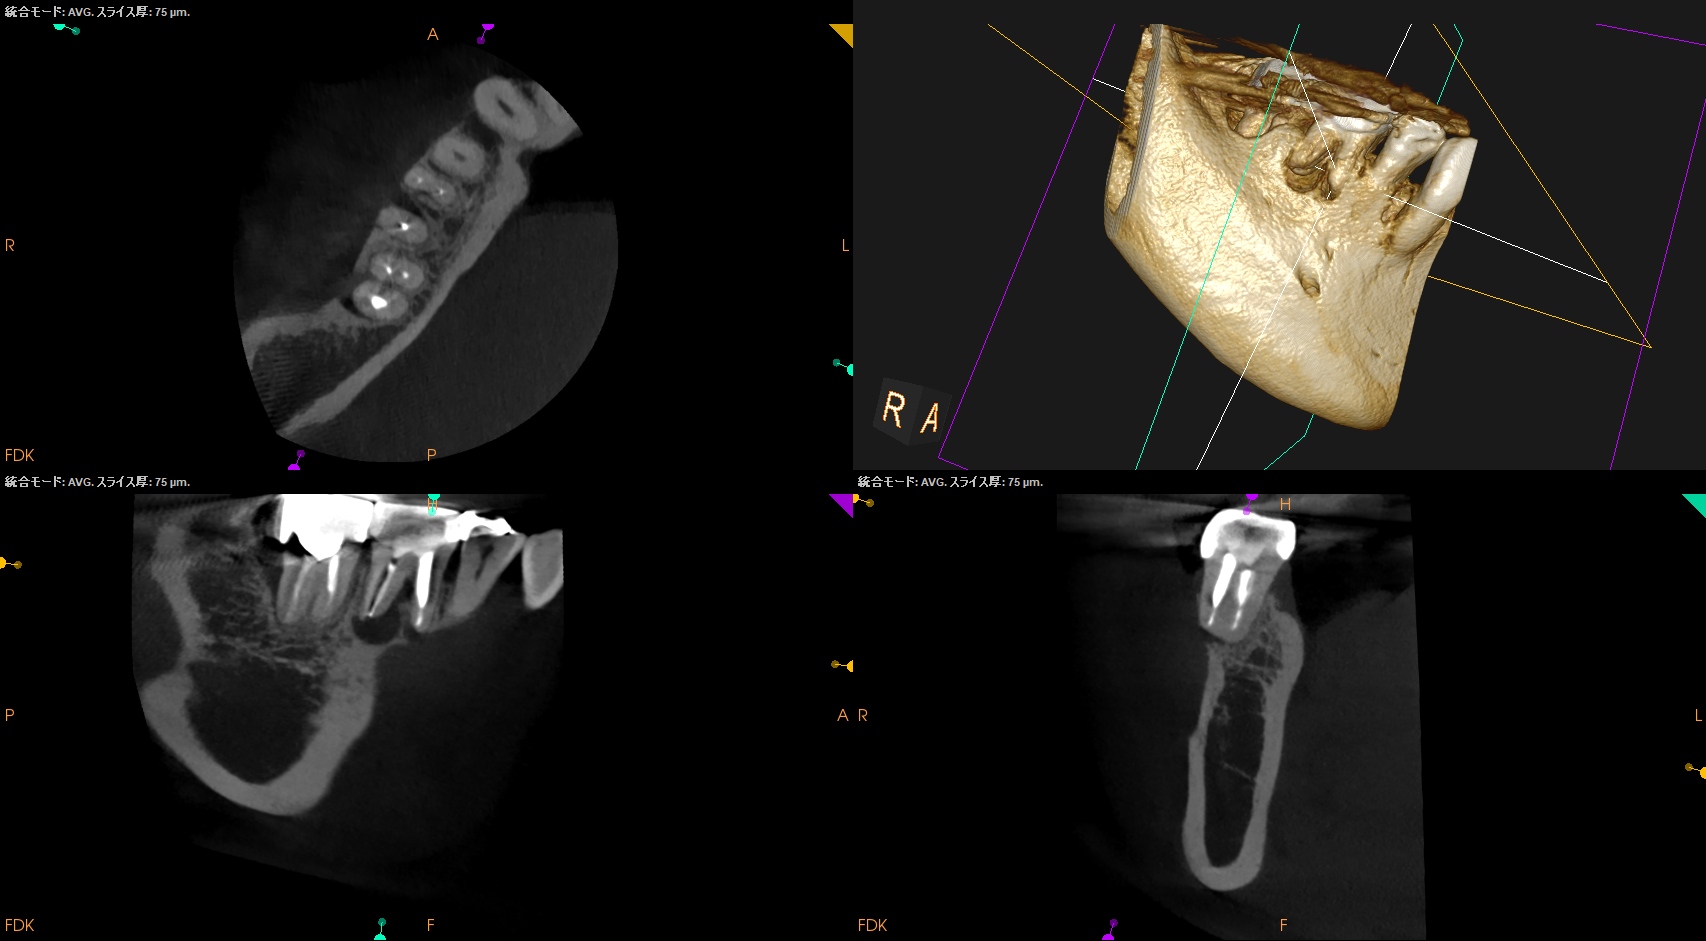

CBCT(2025.9.16)

#30

MB

ML

D

B

頬側の皮質骨が裂開していることが圧痛の原因だろう。

が、Suns tractがないのでApicoectomy!というよりは再根管治療だろう。